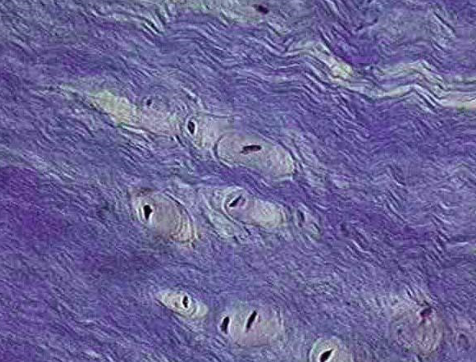

Osteon or haversian system

A Haversian canal, with its surrounding cells and layers of bone,

haversian canal

a microscopic channel in bone tissue that contains blood vessels and nerves

Lamellae

concentric rings of inorganic matrix

lacunae

this is where osteocytes are located

canaliculi

transport network that allows blood vessels to reach osteocytes